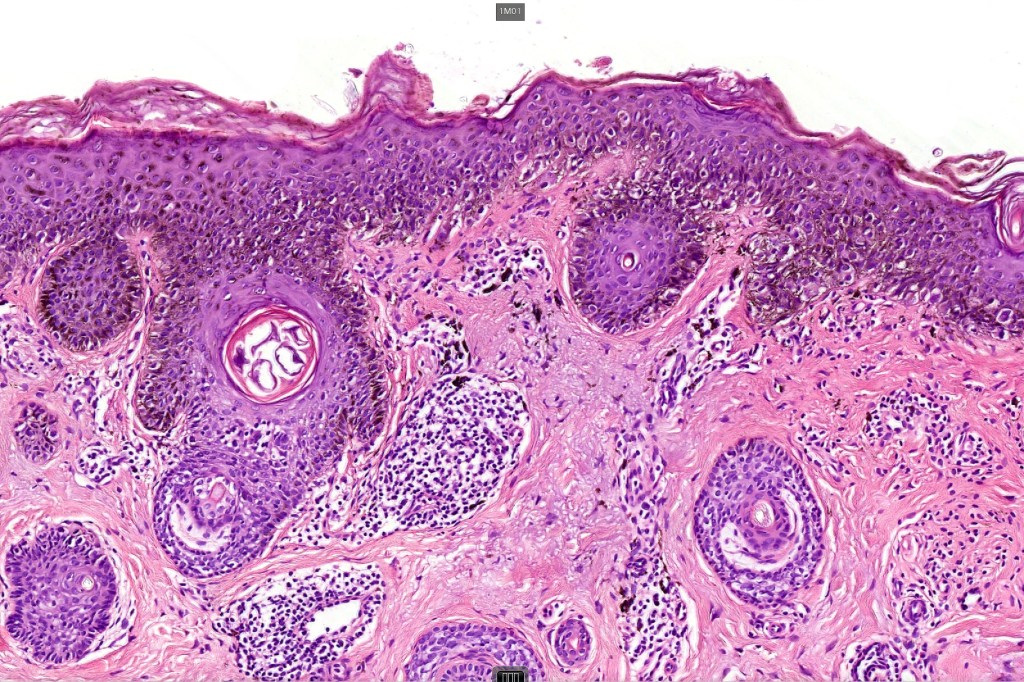

•Epidermal atrophy & solar elastosis

•Atypical melanocytes located predominantly along the basal layer of the epidermis, singly, in short arrays or extensively involving the whole epidermis

•Nest formation present in more advanced cases

•Adnexal involvement

•Pagetoid spread

•Dermal melanophages & lymphocytic infiltration